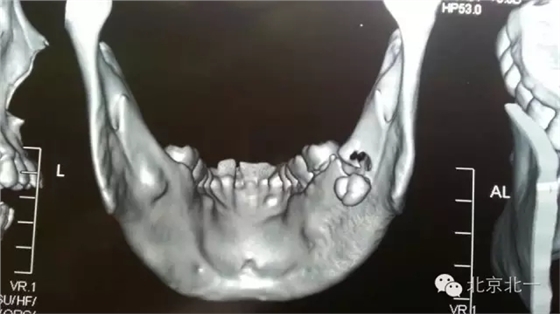

圖二:CBCT重建可見牙根位于舌側(cè)達(dá)到頜下間隙。

圖三:BCBT重建可見牙根貼在下頜骨下緣舌側(cè)面,接近頜下間隙

圖四:CBCT重建不同視覺看牙根位置